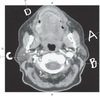

16

Q

A. Pontine cistern

B. Cisterna magna

C. Supercellar cistern

D. Cerebellomedullary cistern

A